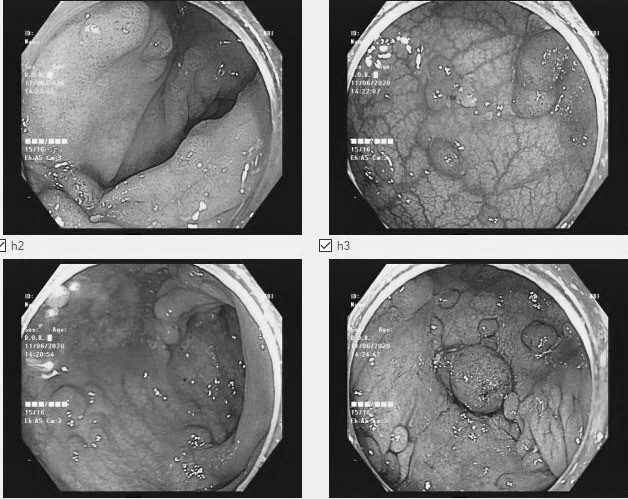

Bác sĩ Nguyễn Văn Dũng, Trưởng Khoa Ung bướu 1, Bệnh viện Bãi Cháy, cho biết trên 100 polyp với các kích thước, hình dáng khác nhau tồn tại trên manh tràng, trực tràng và đại tràng bệnh nhân. Polyp lớn nhất đường kính trên 2 cm, bề mặt nhiều mạch máu nuôi, có vùng mất cấu trúc tuyến và chảy máu tự nhiên. Trực tràng có u sùi nham nhở, dễ chảy máu ở đoạn sát ống hậu môn đến đoạn cách rìa hậu môn 8 cm. Kết quả sinh thiết cho thấy bệnh nhân bị ung thư.

"Đây là ca đa polyp đại trực tràng đã ung thư hóa, xâm lấn tổ chức xung quanh", bác sĩ Dũng nói. Bệnh nhân phải cắt toàn bộ đại tràng, cắt cụt trực tràng và nạo vét hạch, tạo hậu môn nhân tạo.